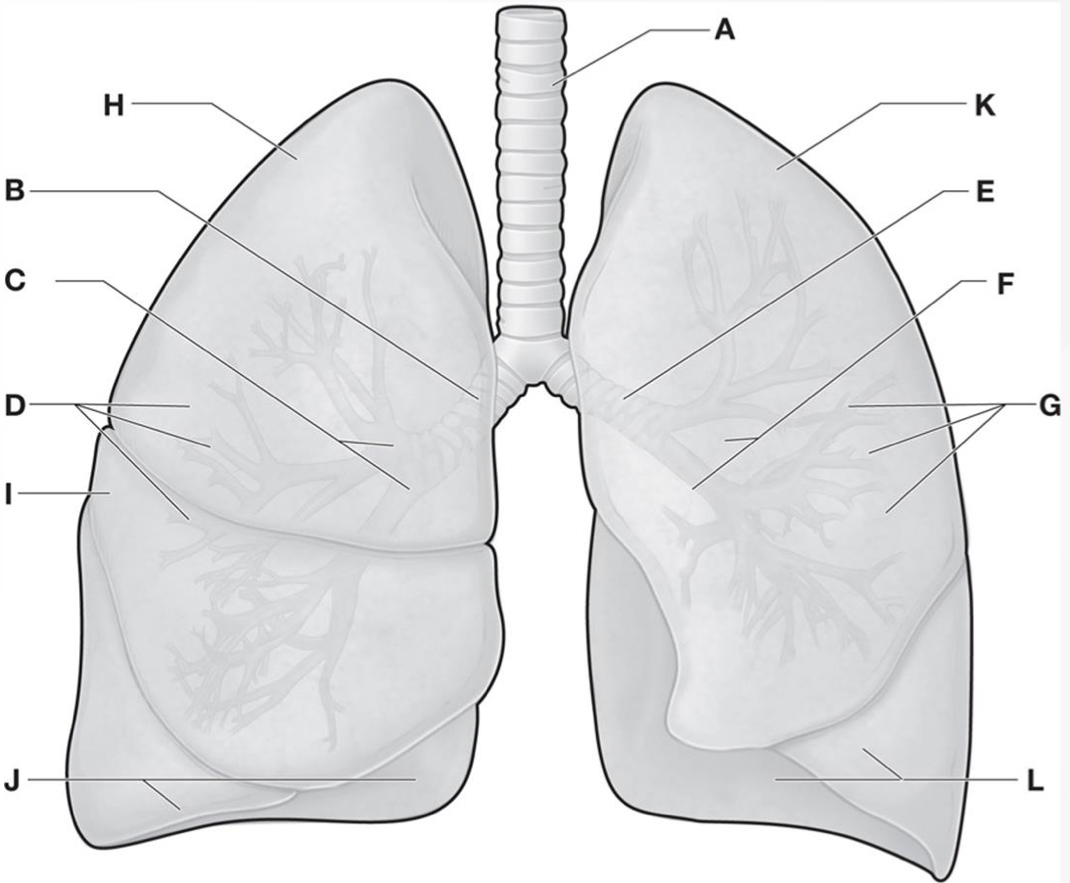

Which letters are the Horizontal & oblique fissures of the Right lung?

A & D

New cards

Which letters are the Superior, middle, & inferior lobes of the Right lung?ย

B, C, & E

Which letter is the Oblique fissure of the Left lung?

G

Which letters are the Superior & inferior lobes of the Left lung?ย

F & H